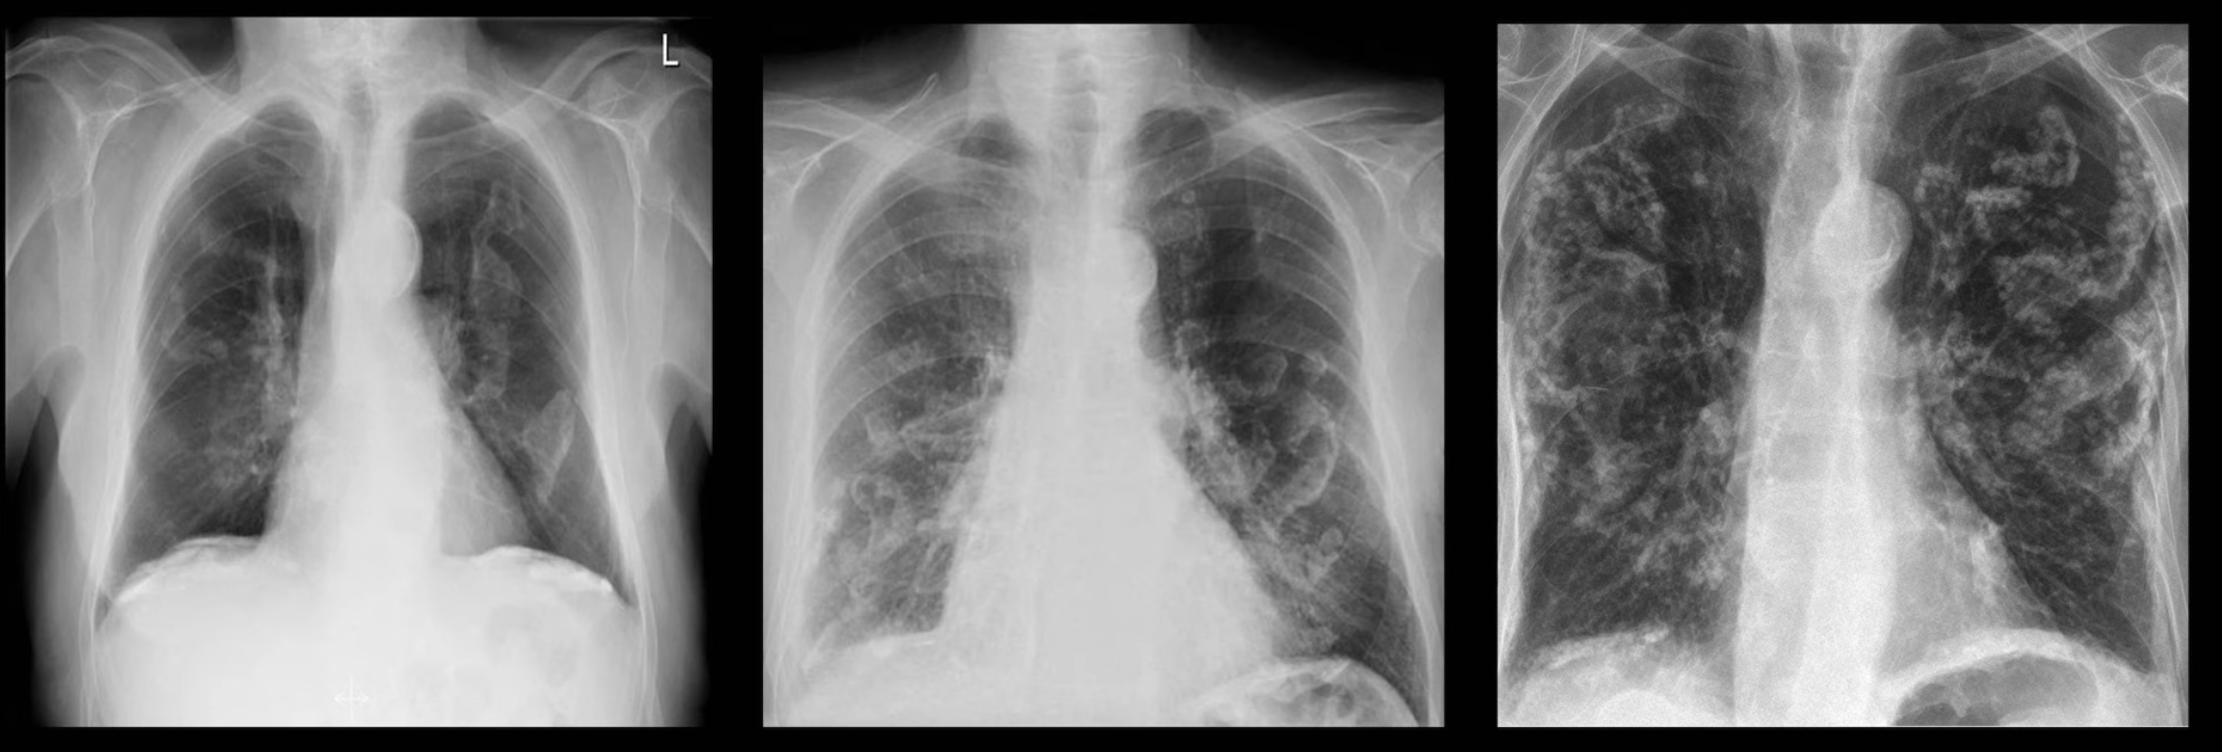

Interstitial Opacities

Further described based on pattern:

Differentials Predominantly reticular: idiopathic pulmonary fibrosis, connective tissue disorders (e.g. scleroderma, rheumatoid arthritis), atypical pneumonia, idiopathic interstitial pneumonia, asbestosis, chronic aspiration, pulmonary drug toxicity (e.g. nitrofurantoin), sarcoidosis, chronic hypersensitivity pneumonitis

Predominantly nodular:

- <2 cm: miliary tuberculosis, fungal infection, silicosis, sarcoidosis

- >2 cm: metastatic cancer, lymphoma, subacute hypersensitivity pneumonitis, granulomatosis with polyangiitis, rheumatoid nodules